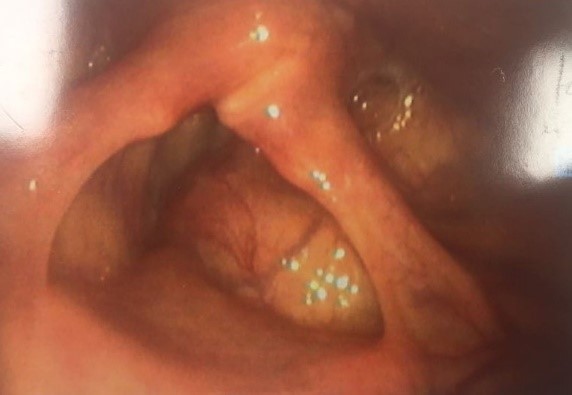

Direct laryngoscopy was attempted but biopsy of the lesion was not possible. The overlying mucosa appeared to be benign (Figure 2).

![]() |

Figure 2. Benign mucosal appearance on endoscopy. |

A provisional diagnosis of a possible laryngocele was made, given the normal mucosal appearances. Despite repeated attempts, it was not possible to direct a laryngoscope into the laryngeal ventricle to assess the larynx appropriately.